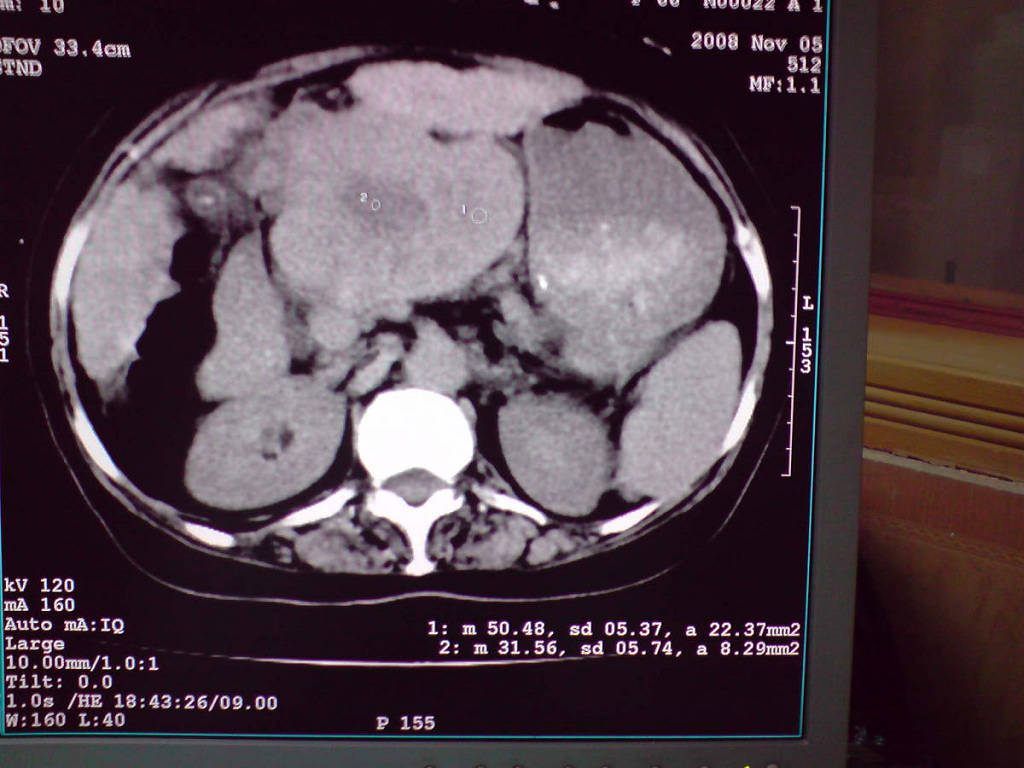

女性,60岁,上腹不适、自感胃部疼痛

小网膜区见类圆形软组织密度肿块,密度不均,内见不规则低密度区,与肝左叶分界模糊,肝脏体积缩小,密度不均匀,边缘呈波浪状,尾状叶明显增大,脾脏下缘明显超出肝脏下缘。

意见:肝硬化并外生性肝癌,建议增强扫描。

肝脏比例失调,形态失常,外缘呈波浪状,腹腔内肿块内见低密度区并与肝脏界限欠清

考虑外生性肝癌,左肺下叶占位,肝硬化

有肝硬化背景,肝胃间隙见不规则形,且密度不均匀的占位性病变,与肝左叶分界不清,首先考虑外生性肝癌可能性大,不排外肝胃间隙恶性占位肝脏受侵可能性。左肺下叶结节影,其内见空泡征,边缘见毛刺,从一元化的角度首先考虑转移。

1 肝脏各叶比例失调,形态失常,外缘呈波浪状。右叶萎缩,左叶 尾叶增大。2 腹腔内软组织密度肿块,低于肝实质密度,内见低密度区,并与肝脏界限欠清。腹膜后见肿大淋巴结,并与腹腔肿块关系密切。3 左肺下叶肿块,见边缘毛刺征及胸膜凹陷征,并与近肺门侧见异常血管相连。

综合考虑:左下肺周围性肺癌伴腹腔 腹膜后淋巴结转移!另:肝硬化!

感谢大家的讨论,今天拿到病理结果是肝细胞癌